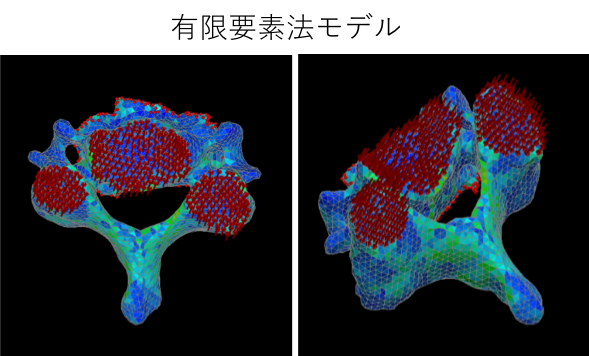

近年の高齢社会において、骨粗鬆症性椎体骨折の患者数は増加しております。そのため、骨粗鬆症診断、骨強度診断がより重要となっています。力学的には強度とは構造と材質により規定されます。力学的に骨強度を定義すると、骨強度は構造的因子と材質的因子により定義されるべきと考えられます。現行の骨密度検査だけでは骨強度は正しく表現されません。現在、骨強度を評価する方法として有限要素法やその他の方法がが用いられ始めております。当科においても骨密度だけでなく、密度分布や骨形状などの構造的因子および材質的因子の一部も反映した骨強度解析を研究しながら、骨粗鬆症性椎体骨折の内服、注射、手術加療をおこなっています。

有限要素法モデル バーチャルリアリティによる椎体破壊試験